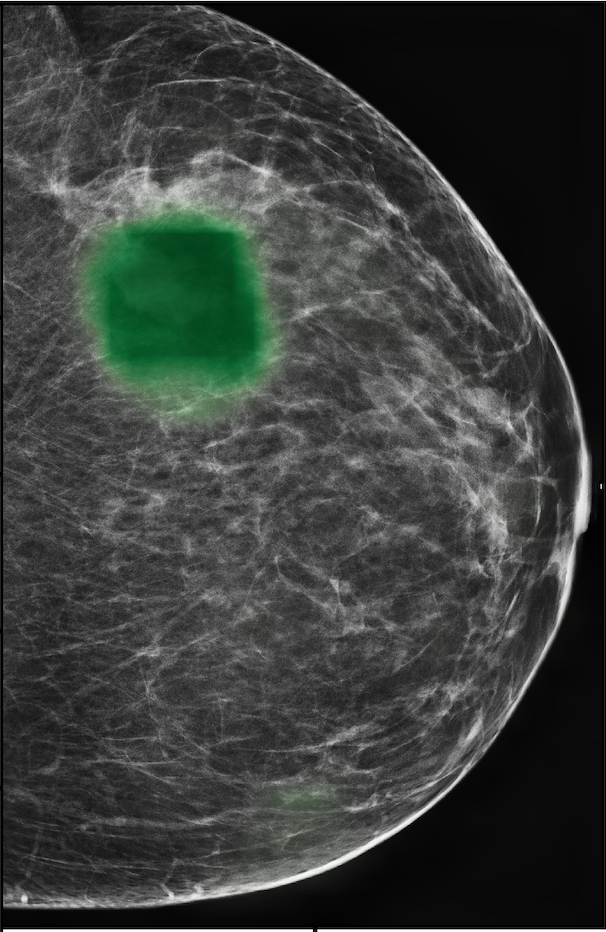

In Figure 7, we visualize saliency maps for four samples selected from the test set. In the first two examples, the saliency maps are highly activated on the annotated lesions, suggesting that our model is able to detect suspicious lesions without pixel-level supervision. Moreover, the attention is highly concentrated on ROI patches that overlap with the annotated lesions. In the third example, the saliency map for benign findings identifies three abnormalities. Although only the top abnormality was escalated for biopsy and hence annotated by radiologists, the radiologist’s report confirms that the two non-biopsied findings have a high probability of benignity and a low probability of malignancy. In the fourth example, we illustrate a case when there is some level of disagreement between our model and the annotation in the dataset. The malignancy saliency map only highlights part of a large malignant lesion with segmental coarse heterogeneous calcifications. This behavior is related to the design of : a fixed pooling threshold cannot be optimal for all sizes of ROI. The impact of is further studied in 3.6. This example also illustrates that while human experts are asked to annotate the entire lesion, CNNs tend to emphasize only the most informative regions. While no benign lesion is present, the benign saliency map still highlights regions similar to that in the malignancy saliency map, but with a lower probability than the malignancy saliency map. In fact, calcifications with this morphology and distribution can also result from benign pathophysiology [42].